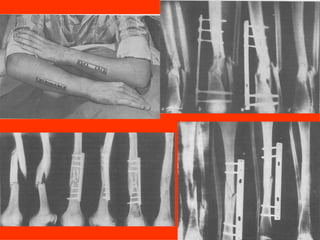

Dal Gennaio 2000 al Febbraio 2006 abbiamo trattato 167 fratture chiuse  con placca percutanea  in 164 pazienti :  27 lesioni diafisarie di gamba, 12 piloni tibiali ,  11 fratture prossimali di tibia, 36 fratture sovracondiloidee di femore, 17 fratture diafisarie di femore, 43 fratture metaepifisarie prossimali di omero, 21 diafisarie d’omero.  156 guarigioni 8 fallimenti

Dal Giugno 2002 al Dicembre 2004 abbiamo trattato 5 fratture esposte: 3 di tibia e 2 di ulna 5 guarigioni

I buoni risultati ottenuti dipendono da 5 punti fondamentali:   una accurata riduzione percutanea della frattura  precise vie di accesso  l’utilizzo della placca che consenta il più lungo braccio di leva possibile il pretensionamento della placca  una sintesi con un ridotto numero di viti

Fratture  esposte